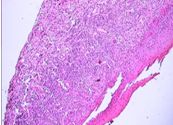

La histopatologia Nº 02-189, realizada en la Cátedra de Anatomía Patológica General y BMF de la Facultad de Odontología, informó que se trataba de epitelio malpighiano con francas hendiduras entre epitelio integro y el corion. El conjuntivo presentaba infiltrado inflamatorio moderado linfoplasmocitario con eosinófilos escasos e hiperplasia endotelial vascular (Foto 5)

Foto 5 Desprendimiento in toto del tejido conjuntivo y presencia de neovasos

El estudio histopatológico (Nº 03-129) realizado en la Cátedra de Anatomía Patológica General y BMF de la Facultad de Odontología, informó que se trataba de una ampolla subepitelial. El epitelio se mantenía en áreas adosado a la membrana basal. El conjuntivo presentaba un infiltrado inflamatorio linfocitario, con neutrófilos, plasmocitos, abundantes mastocitos y neovasos (Fotos 8 – 10).

Foto 8 Hendidura entre epitelio de cubierta y tejido conjuntivo. Ampolla subepitelial

Foto 9 Infiltrado de linfocitos, neutrófilos y plasmocitos

Foto 10 Presencia en conjuntivo de mastocitos y neovasos. Alteración de células basales

El estudio de los tejidos en el microscopio óptico demuestra, una separación nítida entre epitelio y conjuntivo, llamada ampolla o bulla subepitelial. Este epitelio mantiene la capa de células basales y por debajo de él, se observan desde suaves hendiduras a francas luces subepiteliales que se extienden a lo largo de la superficie.

El techo que conforma la parte superior de la ampolla está constituido por un epitelio atrófico y comprimido en todo su espesor. El contenido de estas ampollas es sero-fibrinógeno con eosinófilos y neutrófilos. El inicio de la enfermedad se caracteriza por una reacción inflamatoria rica en eosinófilos y linfocitos, pero con escasos plasmocitos, dispuestos en forma difusa hacia la profundidad del tejido conectivo papilar edematoso.

En general el infiltrado inflamatorio es de grado variable en el tejido conjuntivo, con abundantes células plasmáticas y a veces con presencia de eosinófilos y neutrófilos. Además existe dilatación de los vasos sanguíneos, acompañado por un moderado infiltrado inflamatorio que abarca de la superficie hasta la profundidad del corion.

La repetición de los brotes evolutivos en la misma zona, conduce a la atrofia de las papilas del corion y a la neoformación de los vasos capilares, con reacción fibrosa y acúmulos de densos infiltrados linfoplasmocitarios.